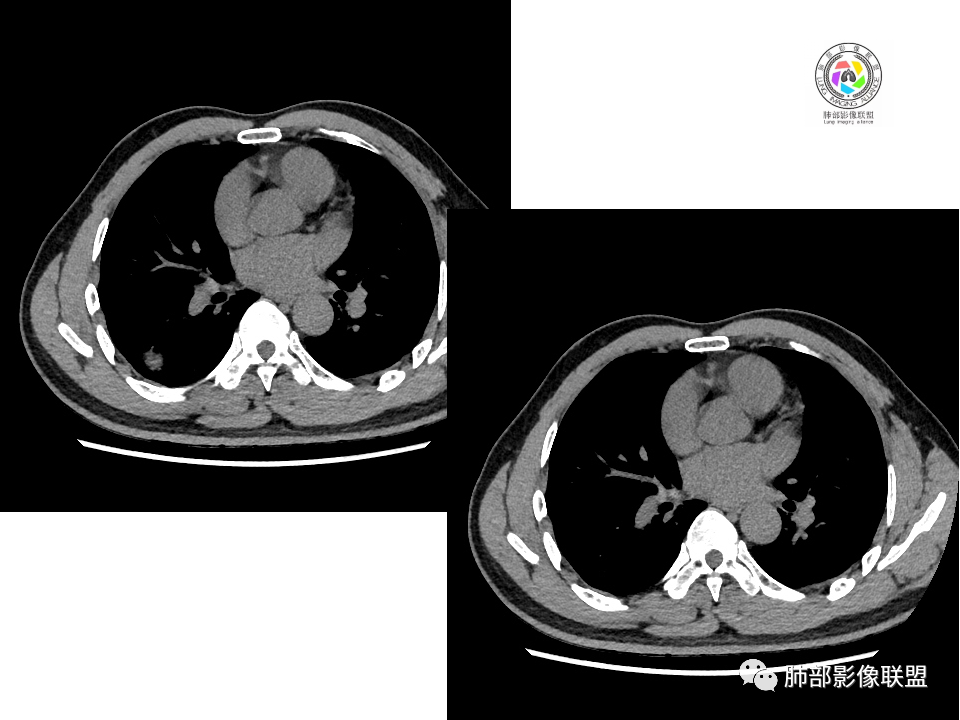

2.右肺下叶背段胸膜下块影,边界清楚光整,上下极见磨玻璃晕,未见明显分叶毛刺和棘状突起,未见胸膜凹陷或胸壁侵入。密度均匀,轻度不均匀强化。未见支气管进入。

3.右肺中叶外侧段胸膜下散在小片影,磨玻璃密度为主,边界不清,支气管相关。符合炎性特征!

4.右肺下叶基底段支气管血管束旁小结节影,边界清楚,强化不明显。注意,这结节在“遥远的”基底段。

显然本例焦点在于背段那个边缘光整的块影!

1.边缘光整干净,大病灶缺乏坏死等,不符合鳞癌影像学特征。尽管有吸烟史,还是偏年轻。

2.边缘光整,会是小细胞癌或是大细胞癌吗?小细胞癌的肺门纵隔淋巴结增大往往十分夸张,该患者不符合。

注意,基底段支气管血管束旁的小结节影,即便是淋巴结,也与背段病灶引流途径不符。